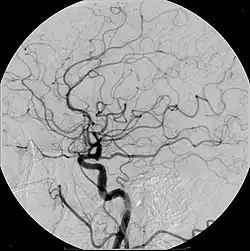

Angiografie bzw. Angiographie (Wortteil Angio- von griechisch ἀγγεῖον ‚Gefäß‘) nennt man in der Medizin die ab 1923/1924 eingeführte radiologische Darstellung von Gefäßen, meist Blutgefäßen mittels diagnostischer Bildgebungsverfahren, beispielsweise Röntgen oder Magnetresonanztomografie (MRT). Hierzu wird häufig ein Kontrastmittel in das Blutgefäß injiziert. Auf dem Bild der aufgenommenen Körperregion zeichnet sich dann der mit dem Kontrastmittel gefüllte Gefäßinnenraum ab. Das resultierende Bild nennt man Angiogramm. Mit der MRT sind auch Angiografien ohne Kontrastmittel möglich, wodurch man sich die invasive Punktion des Gefäßes erspart.

- Die zerebrale Angiografie wurde 1927 von dem portugiesischen Arzt und Politiker António Egas Moniz und dessen Mitarbeiter Pedro Manuel de Almeida Lima als Röntgenkontrastdarstellung des intrakraniellen Gefäßsystems von der Arteria carotis aus entwickelt. Ab 1931 erprobte er auch den Zugang über die Axillararterie und verwendete er als Kontrastmittel das später wieder verlassene radioaktive und giftige Thoriumdioxid.[1] Später wurden andere Kontrastmittel eingesetzt.[2] Die zerebrale Angiografie erfuhr durch die Einführung des Seldinger-Katheters zu Beginn der 1950er Jahre eine Erleichterung ihrer Anwendung.[3]

Zunächst wird ein Katheter oder eine Injektionsnadel in das Gefäßsystem eingebracht und dann im bzw. vor den Abgang des interessierenden Blutgefäßes positioniert. Vor Gabe des Kontrastmittels kann ein normales Bild (Leeraufnahme) von der untersuchten Körperregion angefertigt werden. Wird dann das Kontrastmittel über Katheter bzw. Nadel in das Gefäß gespritzt, werden davon in schneller Abfolge Aufnahmen angefertigt. Sollten diese Bilder in digitaler Form gespeichert werden, kann man von den Angiografiebildern die Leeraufnahme subtrahieren. Störende Bildelemente, die auf beiden Bildern vorhanden sind (z. B. Knochen), werden dadurch ausgeblendet, was die Auswertung der Aufnahmen erleichtert (digitale Subtraktionsangiografie).